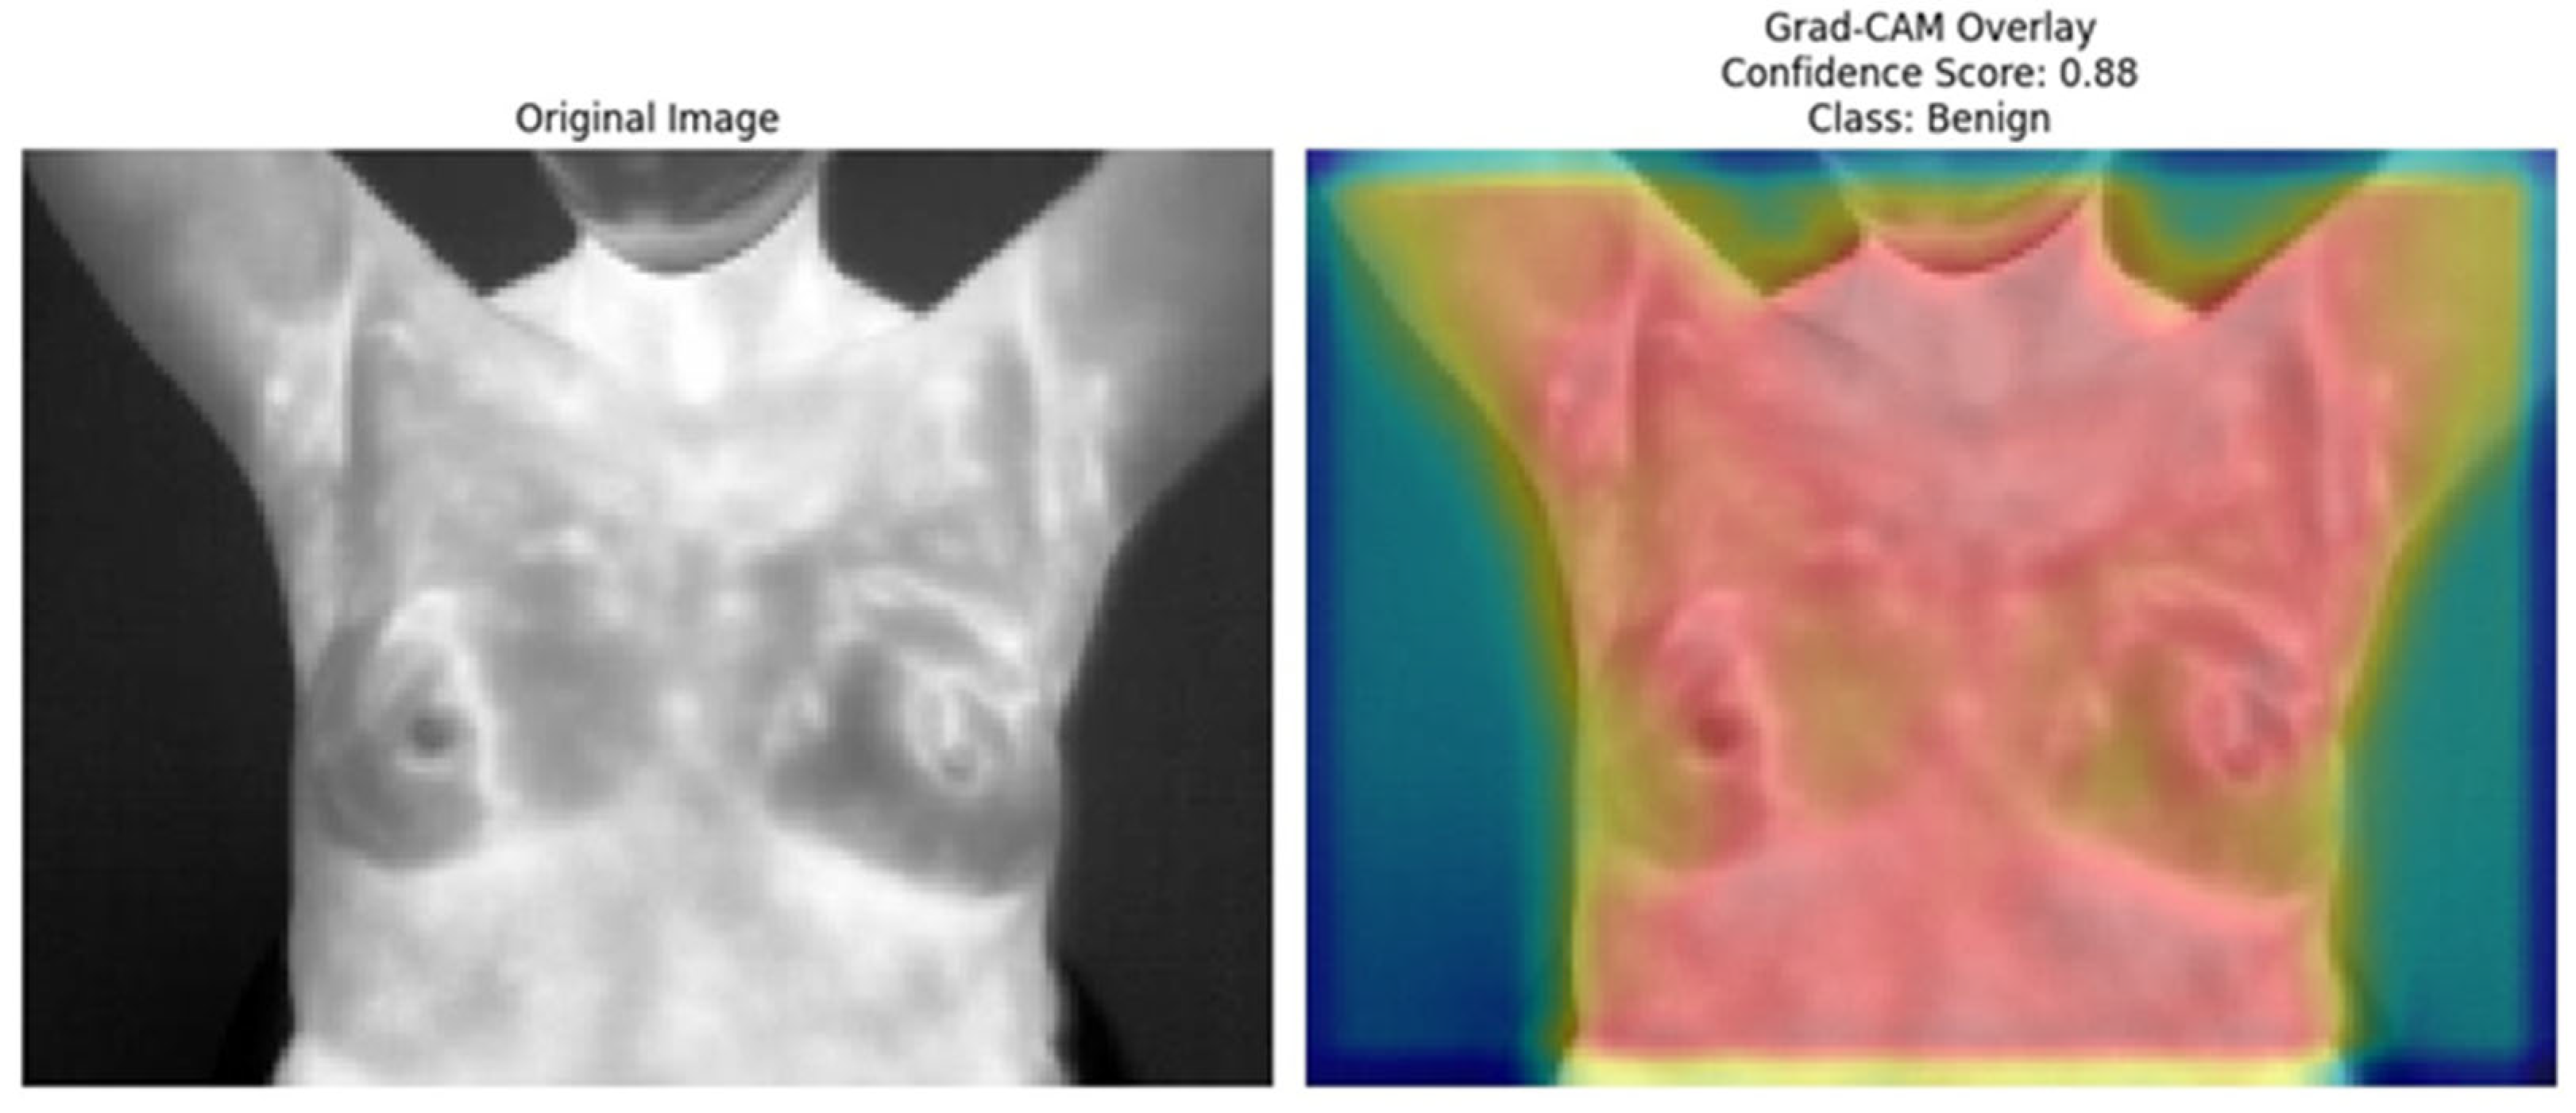

The Grad-CAM [41] overlays provide an essential layer of explainability to the ResNet152 + SVM model by highlighting regions of interest (ROI) that significantly influence the model’s predictions. These heatmaps, specific to each predicted class (e.g., normal, sick, malignant, benign), offer class-specific activation maps, shedding light on how the model differentiates among categories. By incorporating confidence scores (e.g., 0.80, 0.85) alongside these visualizations, clinicians can better understand and trust the model’s decision-making process. This approach directly addresses the “black-box” nature of deep learning models by visually explaining their predictions. Moreover, Grad-CAM overlays emphasize biologically relevant regions, such as abnormal heat patterns [56], as depicted in Figure 15, Figure 16, Figure 17, Figure 18 and Figure 19, enhancing the model’s interpretability and robustness in feature extraction. These insights validate the model’s focus areas against clinical knowledge and bridge the gap between AI-driven predictions and practical clinical applications, paving the way for greater trust and usability in real-world diagnostic settings.